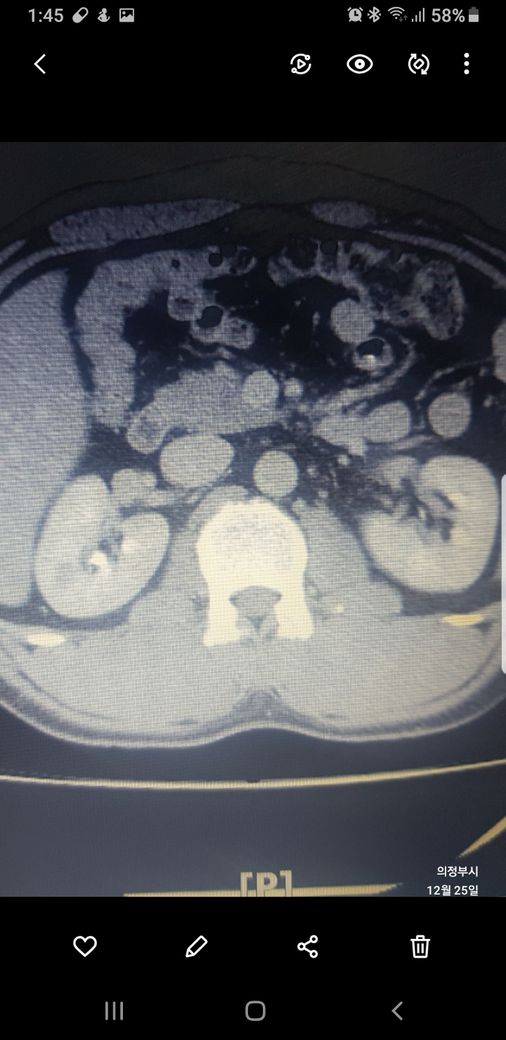

복부ct 작년 11월 , 올해 12월 촬영분입니다.

우측신장에 작년에는 1.7cm 물혹이 올해는 같은곳에 1.2cm 출혈성낭종이라는데

사진 1~4번째 는 작년

둘다 같은 병변이고 비조영증강에서 약간의 고음영 소견이 있어 출혈성 낭종이 의심됩니다.

신장의 낭성병변의 분류에서 1, 2, 2F, 3, 4이렇게 나뉘는데, 2에 해당되는 소견입니다.

크게 걱정하실 필요는 없습니다.